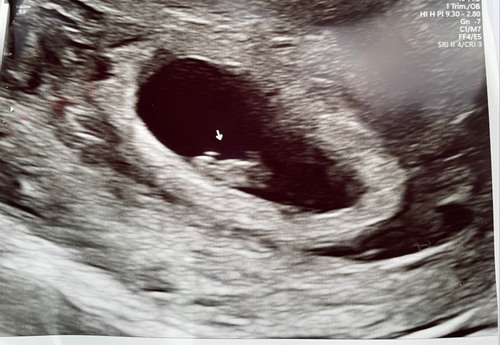

Ik was al verder dan gedacht en met 9+4 te laat voor de theorie, maar je ziet hier wel 2 lichte plekken en in het echt is het nog een stuk duidelijker verschil. Die langrekte witte streep links/onder bij de baby is waar je dan op hoort te letten. (Dit was bij mij uitwendig. En als het dus optijd zou zijn was het een jongen volgens de theorie.)

Het dooier zakje leek rechts te zitten toen ze inzoomde